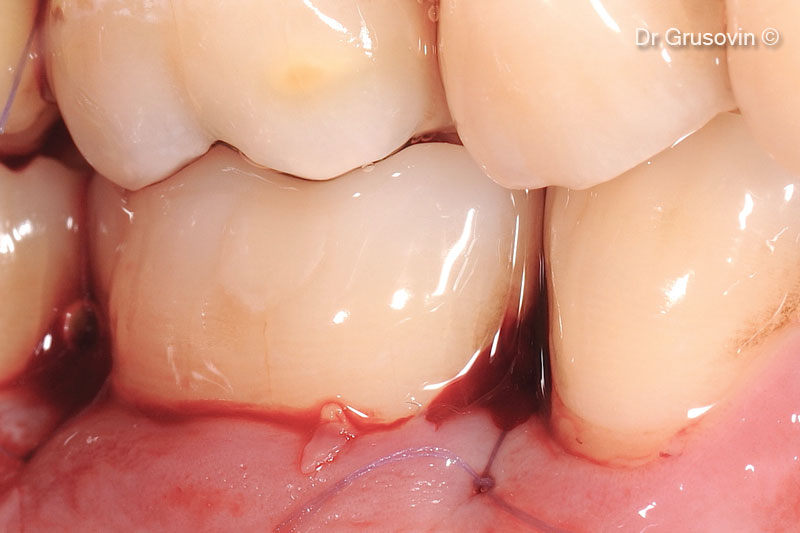

4. Clinical view during surgery: vestibular and distal furcation III involvement